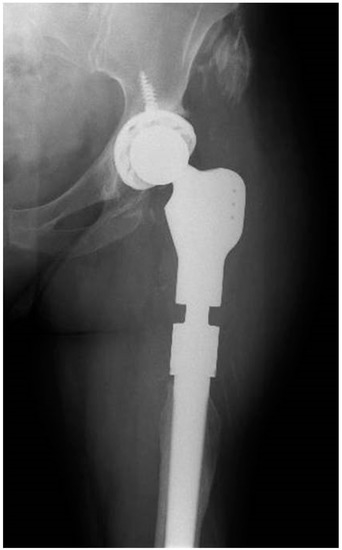

2.2. Case 2